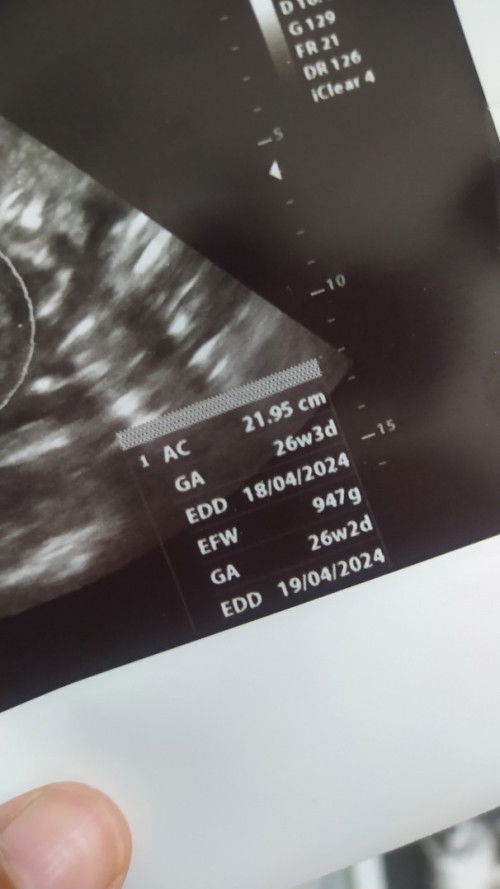

Hasil USG 26week

Bun mau tanya kalau AC itu panjang janin apa bukan ya? Soalnya kalau liat rata rata 26weeks itu udah 30cm ke atas.. Tadi lupa nanya sama dokternyaa #seriusnanya #bantusharing